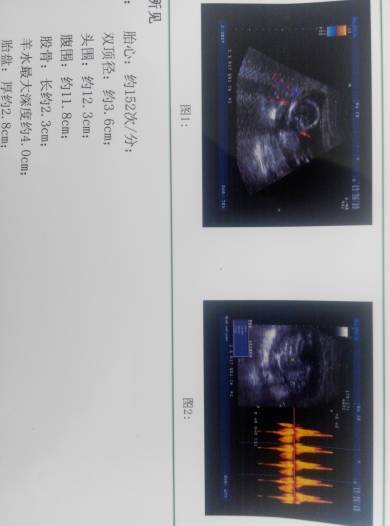

亲们帮我看看这是男是女啊,男女都好,我只是想提前准备宝宝衣服 点击展开 雨的偶然 2015-02-15 14:52 为您推荐: 其他回答 您这数据是不能辨别男孩还是女孩的,建议您找熟人检查b超看看,比较准确,也可以做羊水穿刺来确定, laojianghu309 2015-02-15 14:56 相关问题 求大神解答,我这孩子是男是女,我不男女,我给我孩子准备衣服,谢谢啦 6个月肚肚照,会通过肚肚形状看男女的进来,帮我看看是男是女 帮我看看宝宝正常吗?可以看出男女不?